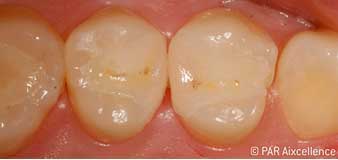

Рис. 2. Освещение зондом Facelight используется здесь в качестве трансиллюминации для распознавания непрозрачных областей. Соединения порфирина при такой форме освещения не активируются